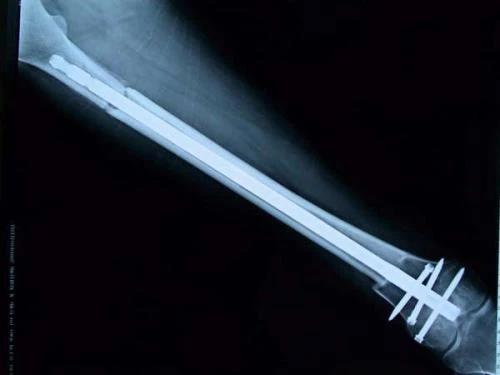

保肢治療指經(jīng)典型骨肉瘤在多學科團隊醫(yī)生共同努力下完成的新輔助化療、保肢手術和輔助化療等一系列治療總稱,其目的是在提高患者生存率的前提下,減少局部復發(fā)、盡量保留良好的肢體功能。肢體經(jīng)典型骨肉瘤保肢治療方法如下圖所示: